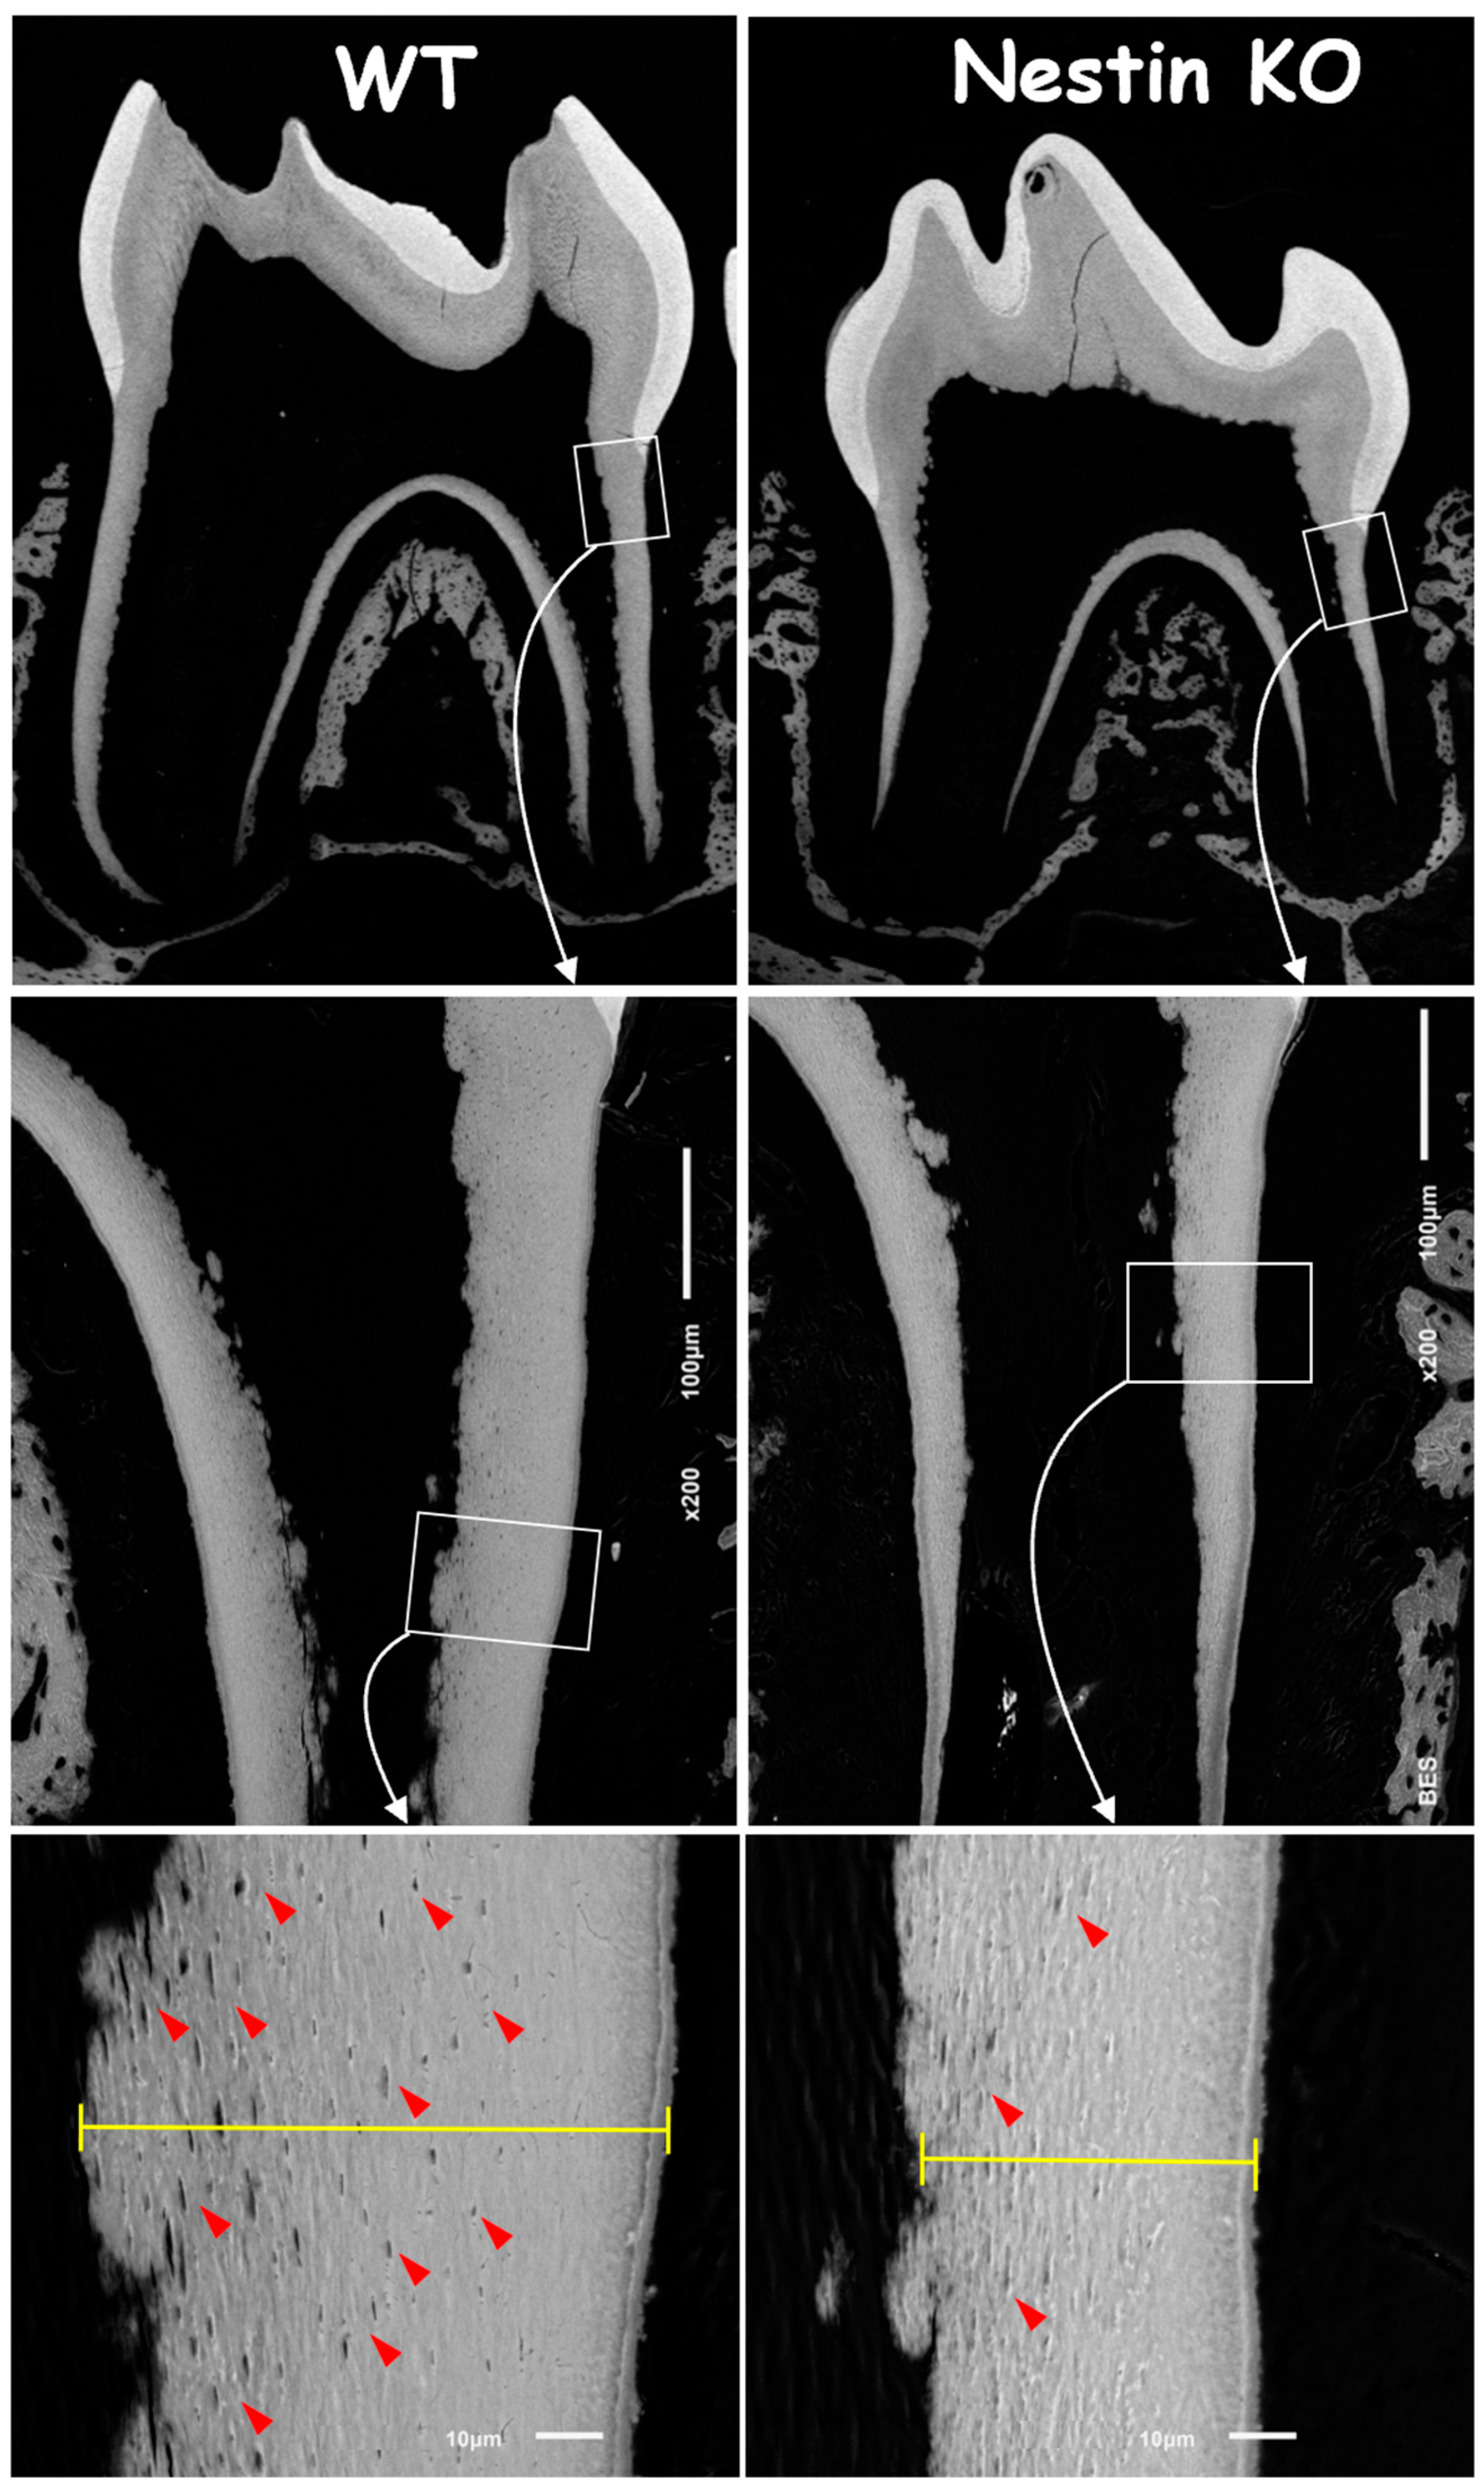

3.2. Nestin KO Mice Displayed Malformed Dentin Tubules in Roots